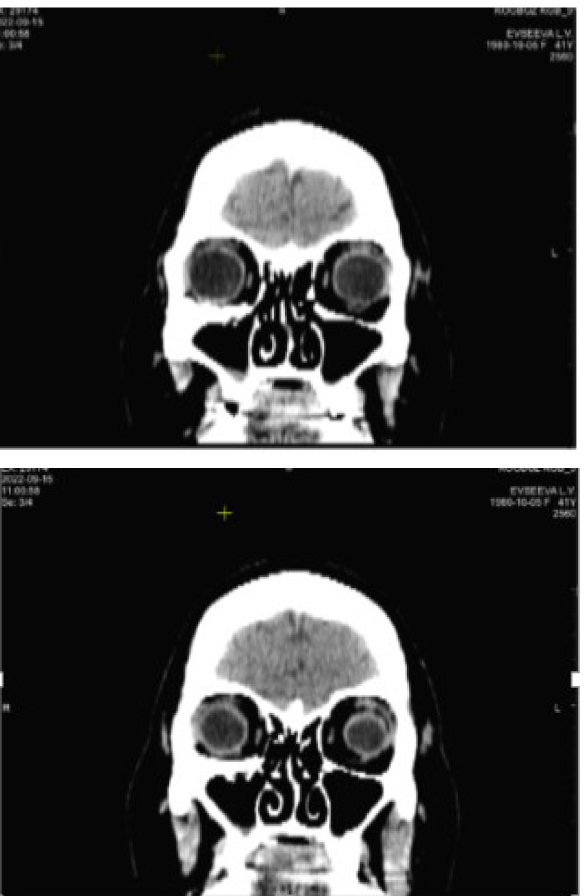

По данным КТ сохраняется расширение объема правой орбиты за счет смещения нижне-внутренней стенки до 10 мм на границе задней трети. Высота нижней стенки локально восстановлена за счет узкого костного трансплантата, расположенного аксиально на границе наружной трети (рис. 9).

Рис. 9. Компьютерная томография орбит до операции. Клинический пример 3